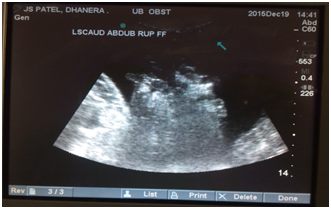

The eye mucus membrane was pale to pale-pink in four and congested in five calves. Similar observations were noted by Parrah et al.,2 and Tamilmahan et al.,6 in urinary retention cases. The mean heart rate, respiration rate and temperature were found within normal physiological limit at the time of presentation and on 12th day after surgery (Table 2). However Kushwaha et al.,3 and Tamilmahan et al.,6 observed tachycardia and tachypnoea with normal rectal temperature in buffalo calves with urolithiasis. Ultrasound is a non invasive diagnostic tool used for examination of urinary bladder, as small bladder cannot be detected by abdominal palpation or radiography.7 Trans-abdominal B-mode ultrasonograhic examinations with 3.5-5.0MHz transducer visualized the urinary bladder in all calves. In present study free fluid in abdomen and empty urinary bladder with floating abdominal organs (Figure 4), mainly intestine were observed in 6 calves with cystorrhexis, while in one calf subserosal urinary bladder rupture was observed, indicated by distended urinary bladder along with free fluid in abdomen. Similar findings were recorded in cases of urinary bladder rupture by Parrah et al.2 In two calves distended intact urinary bladder was imaged with dilated neck (Figure 5) having multiple hyper echoic foci without acoustic shadow which might be urinary sediments. Parrah et al.,2 have reported hyperechoic foci in distended urinary bladder of calves suffering with obstructive urolithiasis.

Figure 4 Real time B-mode ultrasonogram of caudal ventral abdomen showing free fluid in abdomen.